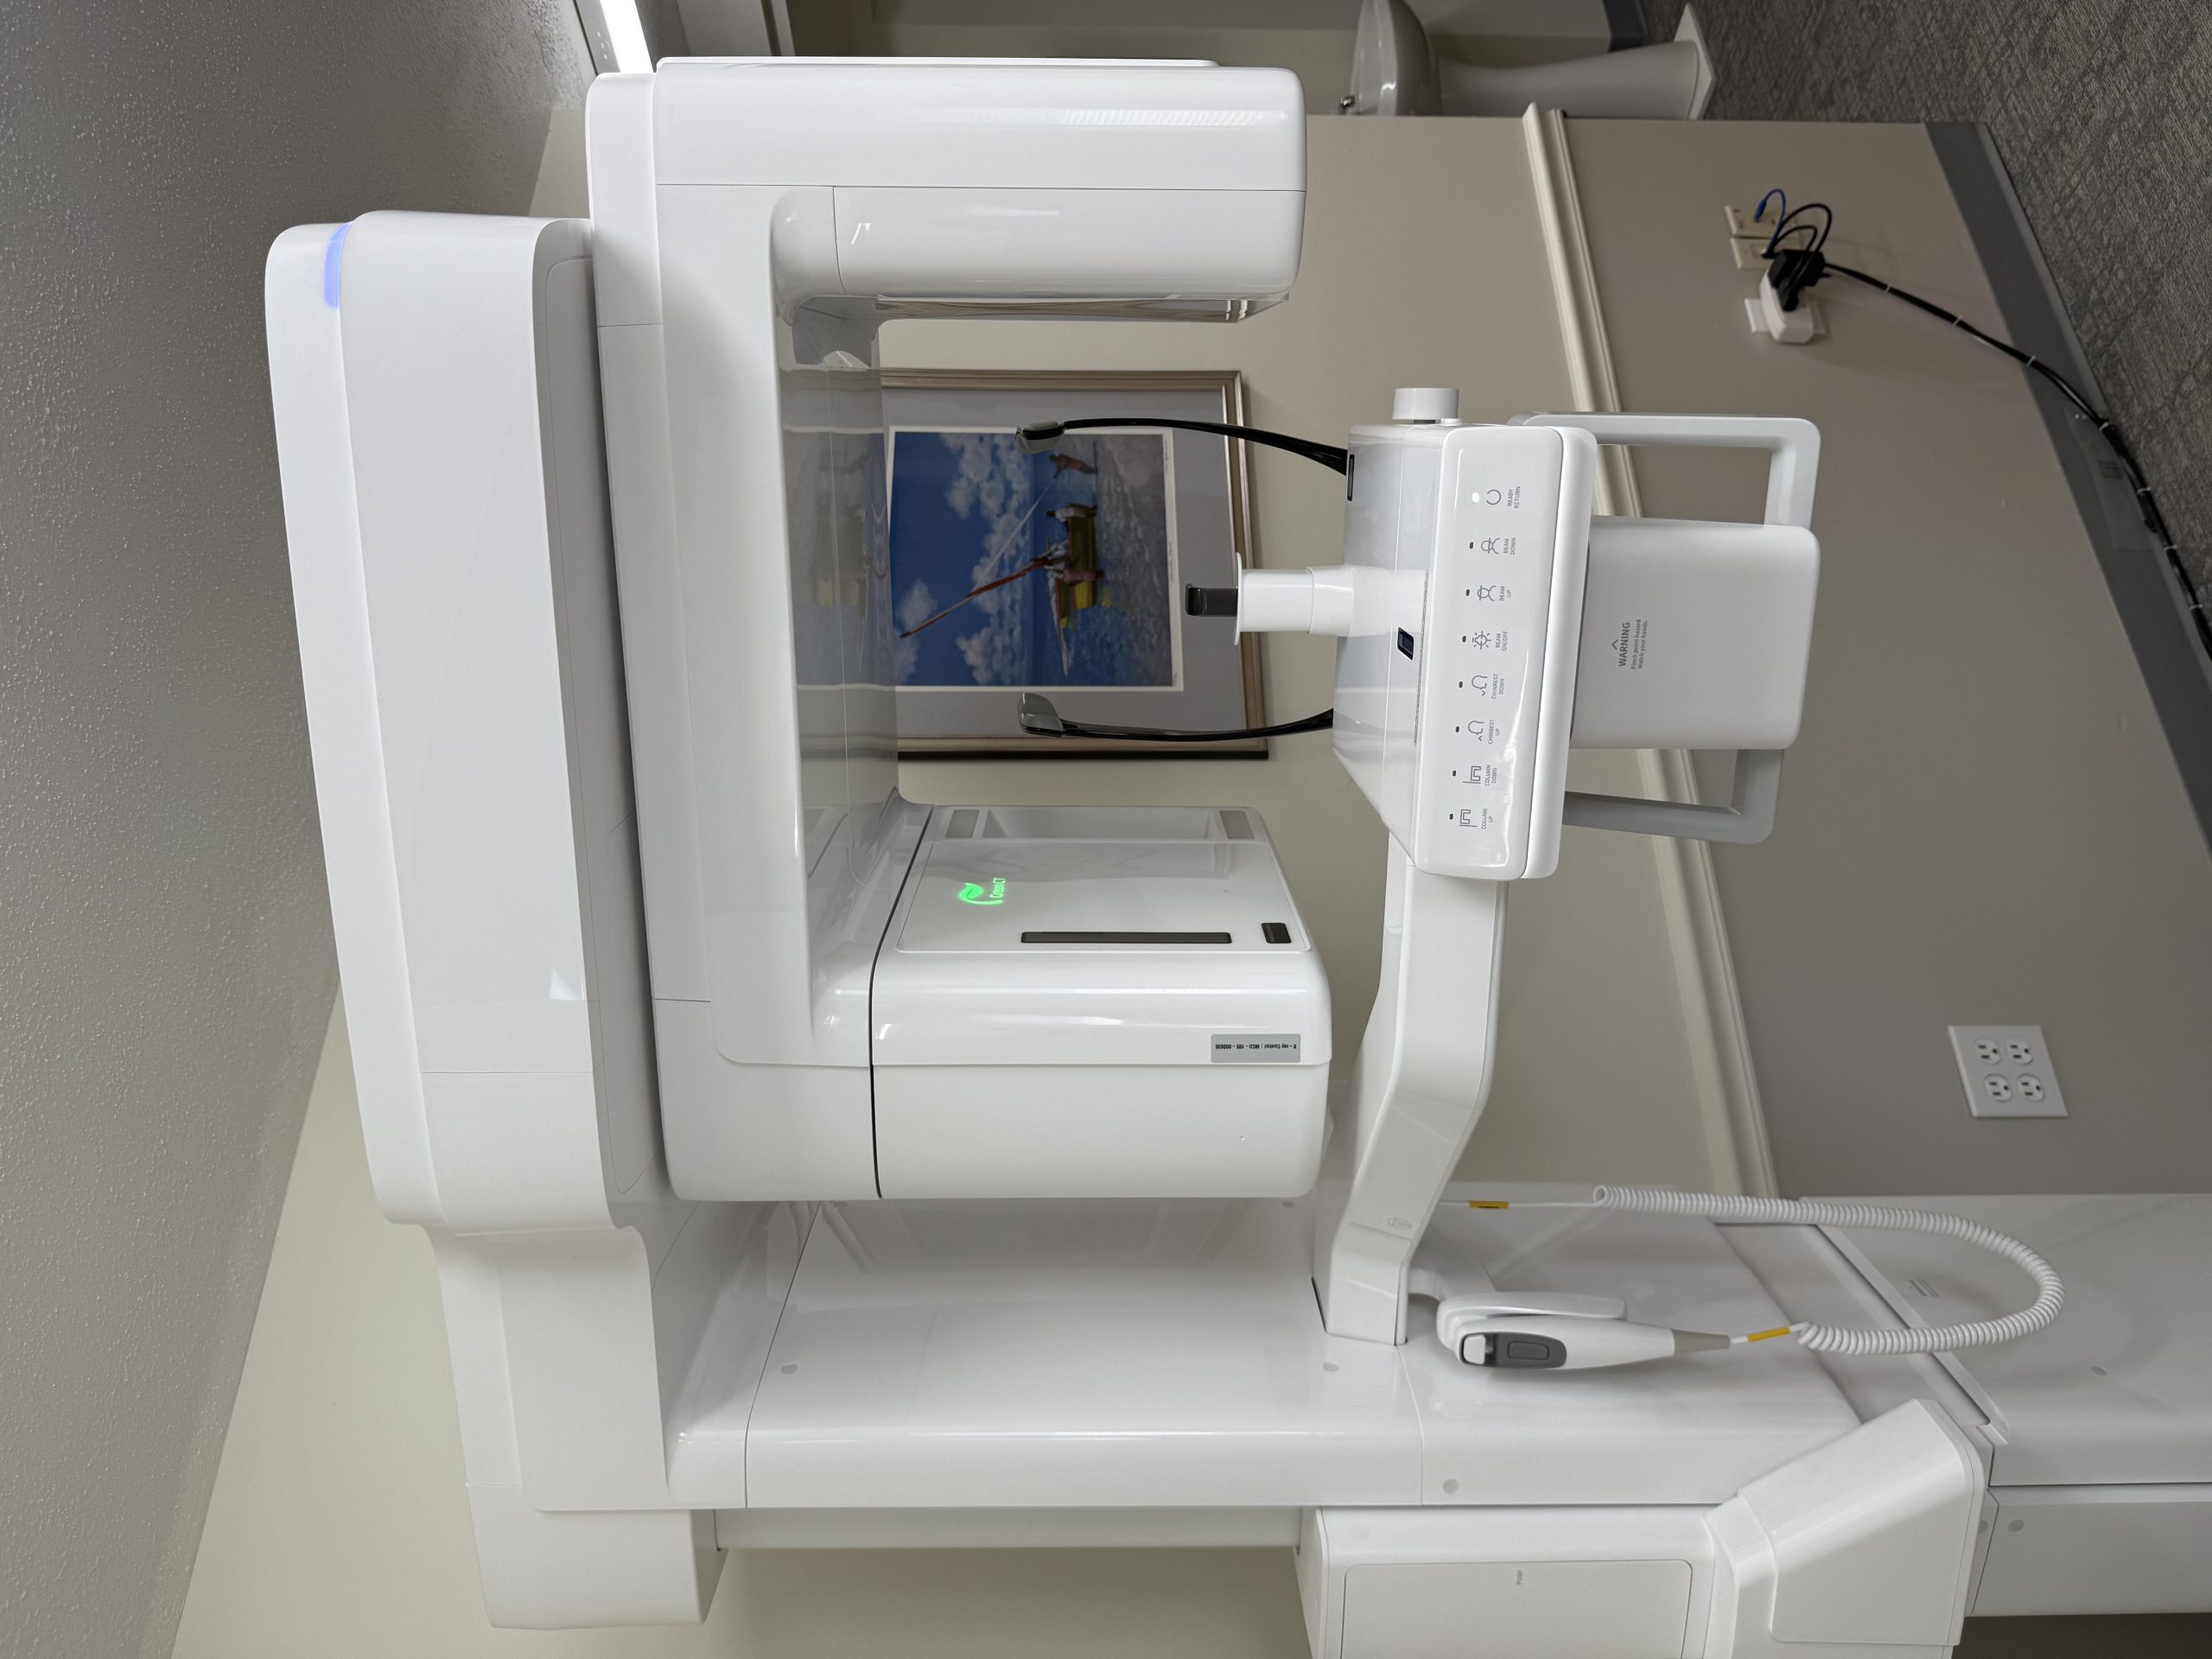

At our practice, we are committed to providing personalized, patient-centered care. We recognize that each individual’s treatment plan is unique, and we give it the careful attention it deserves. Dr. Gulino’s compassionate demeanor, coupled with his extensive knowledge and experience, ensures that every patient feels at ease throughout their treatment. Our offices are equipped with the latest technology, allowing us to continually enhance our care and offer the best possible outcomes for you.

Office Gallery